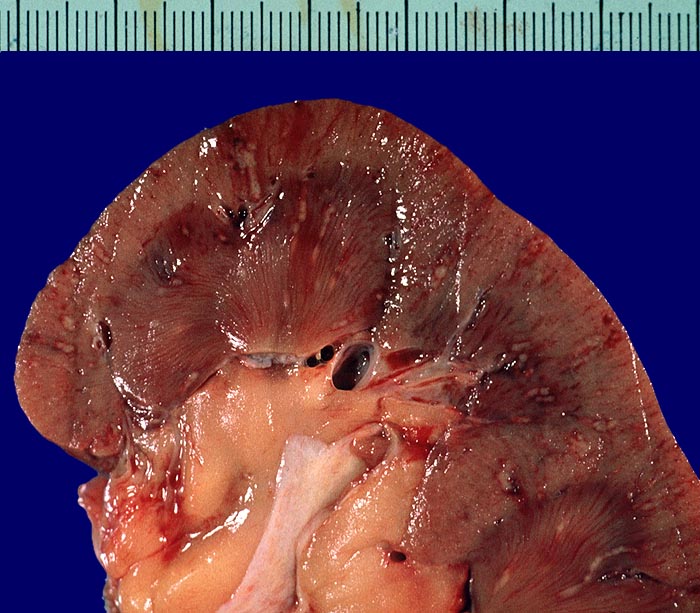

PathoPic ID 2941 - Septikopyämische Herde

Septikopyämische Herde

Entzündung infektiös

Niere

Niere, Harnwege

Zahlreiche in Mark und Rinde gelegene, wenige Millimeter grosse

gelbe Eiterherde umgeben von einem hämorrhagischen roten Randsaum.

Endokarditis

Makroskopie

51